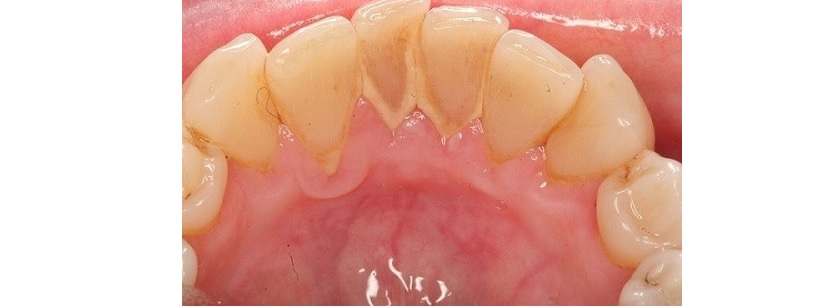

Răng bị nha chu viêm

Vệ sinh răng miệng không tốt, thức ăn đọng lại ở các kẽ răng, nằm sâu ở dưới lợi mà không được lấy hết đi, không thường xuyên đi lấy cao răng (cạo vôi răng), vật nhọn đâm vào lợi như xỉa răng bằng tăm,... là những nguyên nhân gây nên bệnh viêm lợi (viêm nướu). Khi lợi bị viêm, bạn sẽ thấy miệng hôi, lợi dễ chảy máu khi đánh răng hoặc lợi chảy máu tự nhiên, lợi sưng nề, đỏ, phì đại che một phần thân răng.